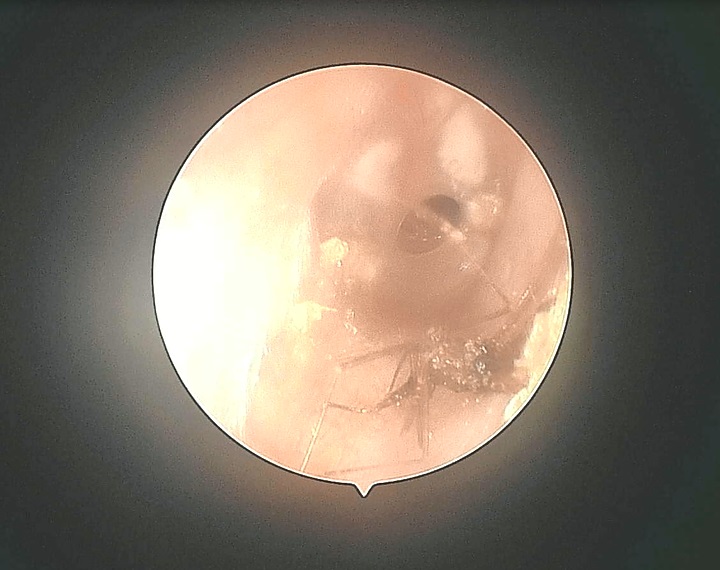

就在这天下午,耳鼻喉科门诊又接诊了一位同样是右耳钻进虫子的赵先生。凌晨,赵先生正在熟睡中,突然感觉右耳有点痒。 起初他并没有在意,想着睡一觉就好了,后来感觉得耳朵里面有东西在动,尝试用各种办法掏耳朵,却是无能为力,越弄越痛,赵先生这下可慌了,急忙来到市二院,医生检查发现,在他的右耳内,竟然有一只蚊子!这可把赵先生吓坏了,怪不得一直感觉耳朵不舒服。